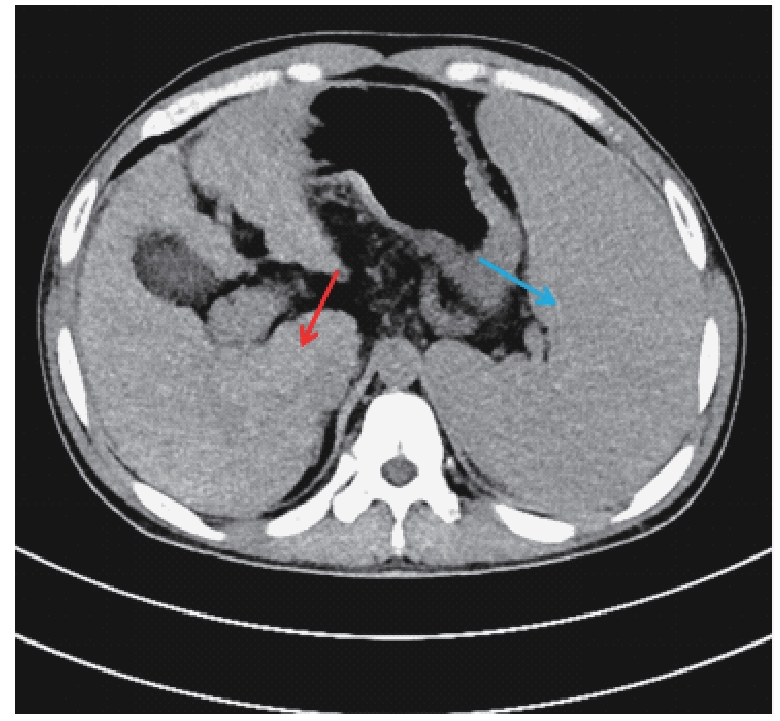

Tao Z, Zhou J F, Jiang Z Z, et al. Hepatolenticular degeneration-induced hepatic dysfunction with extremely atypical clinical manifestations: a case report[J]. Front Med, 2025, 12: 1599283.

|